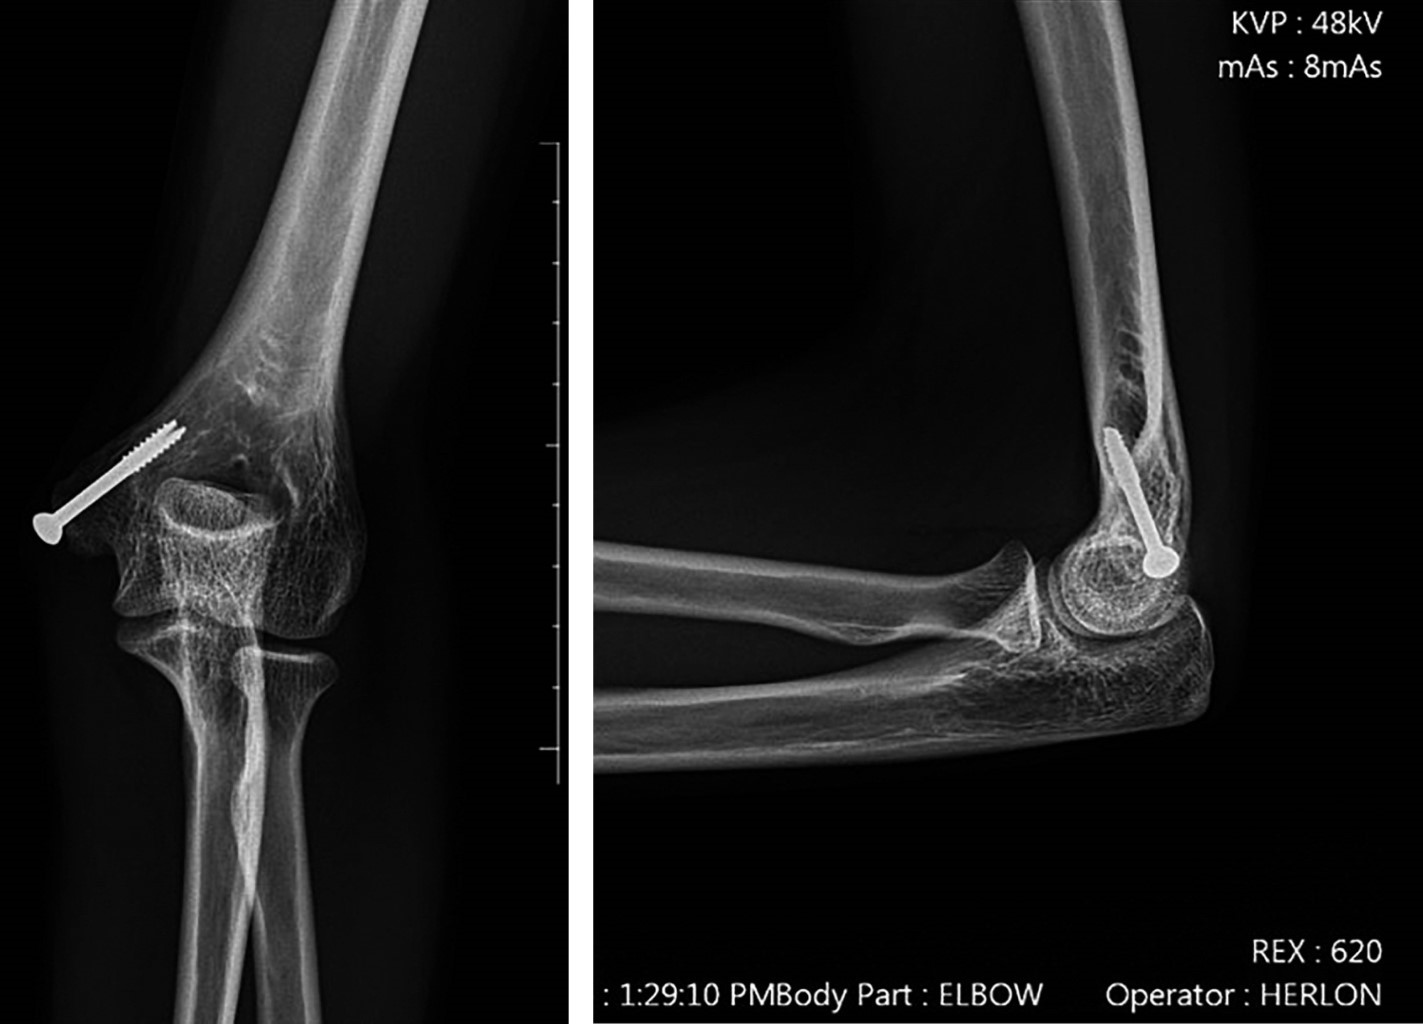

Surgical treatment of the medial epicondyle fracture of the humerus using the ''Inside-out'' technique. Description of the technique and results

Introduction: the "Inside-out" technique is one of the options for medial epicondyle fracture fixation of the humerus. It involves preparing the fixation from the internal portion of the fracture to the external portion. Then, the fracture is fixed with a cannulated screw from the external to the internal portion. This study aims to describe our experience with this technique, its outcomes, and its complications. Material and methods: this is a retrospective observational study describing a series of cases treated with the "Inside-out" technique for medial epicondyle fracture fixation from 2020 to 2024. We evaluated demographic data, follow-up duration, intraoperative events, postoperative complications, and functional outcomes. Results: we analyzed 21 patients, 61.9% of whom were male, with a mean age of 13 years and a mean follow-up period of 19 months. Among these, 71.4% had fractures in the right upper limb, with the most prevalent trauma mechanism being a ground-level fall. No open fractures were observed. A total of 38% had dislocated elbows with an incarcerated medial epicondyle, and one patient had an associated fracture. There were no intraoperative complications. One patient had a 5-degree extension limitation, all fractures achieved consolidation, and no postoperative neurological injuries or valgus instability were observed after fixation. Four patients reported discomfort at the site of the screw head insertion, and one patient complained of a hypertrophic scar. The functional assessment using the QuickDASH score yielded an average of 1.1. Conclusion: the "Inside-out" technique provided secure fixation of the medial epicondyle, preventing its fragmentation, ensuring fracture consolidation, allowing early mobility, and resulting in minimal complications.

Figure 2